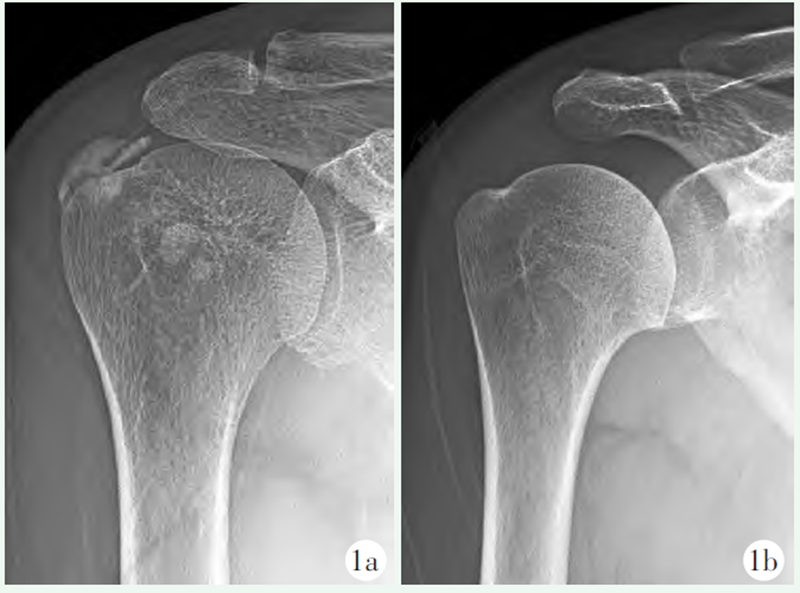

查体:右肩呈被动体位,左手托举右肘。右肩峰前下部压痛,肩关节活动受限。右肩关节X线示:肩峰下高密度片状阴影(图1a),临床诊断钙化性冈上肌腱炎。

患者5周后入院,疼痛较前有所缓解,但仍影响肩关节部分功能,完成术前常规检查后,全麻下行肩关节镜探查。术中反复探查肩峰下间隙与盂肱关节,均未发现钙化病灶并且肩袖完好。术中进行X线片透视检查也未发现钙化灶,于是射频清理增生的炎性滑膜结束手术。术后右肩关节X 线片检查示:肩峰下高密度片状阴影完全消失(图1b)。

图1 a: 术前X线片示肩峰下高密度阴影;b: 保守治疗5周后,镜下未发现病灶,术后右肩关节X线片示肩峰下高密度片状阴影完全消失